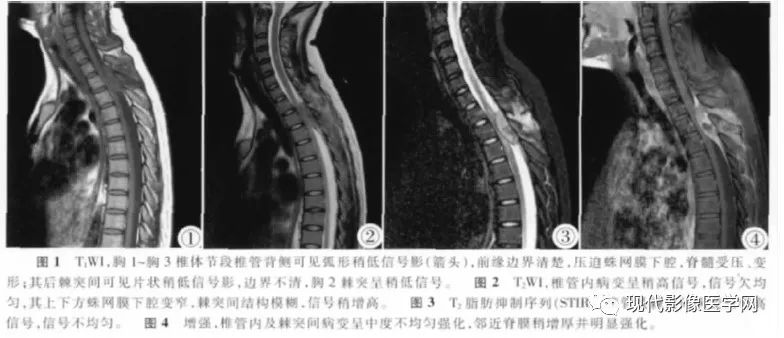

附3例椎管内PNET(来自文献)